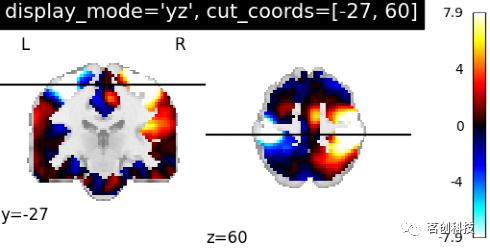

设置display_mode= 'yz',cut_coords=[-27, 60],表示在y和z方向上切割,手动定位。

plotting.plot_stat_map(stat_img, display_mode='yz',

cut_coords=[-27, 60],

title="display_mode='yz', cut_coords=[-27, 60]")